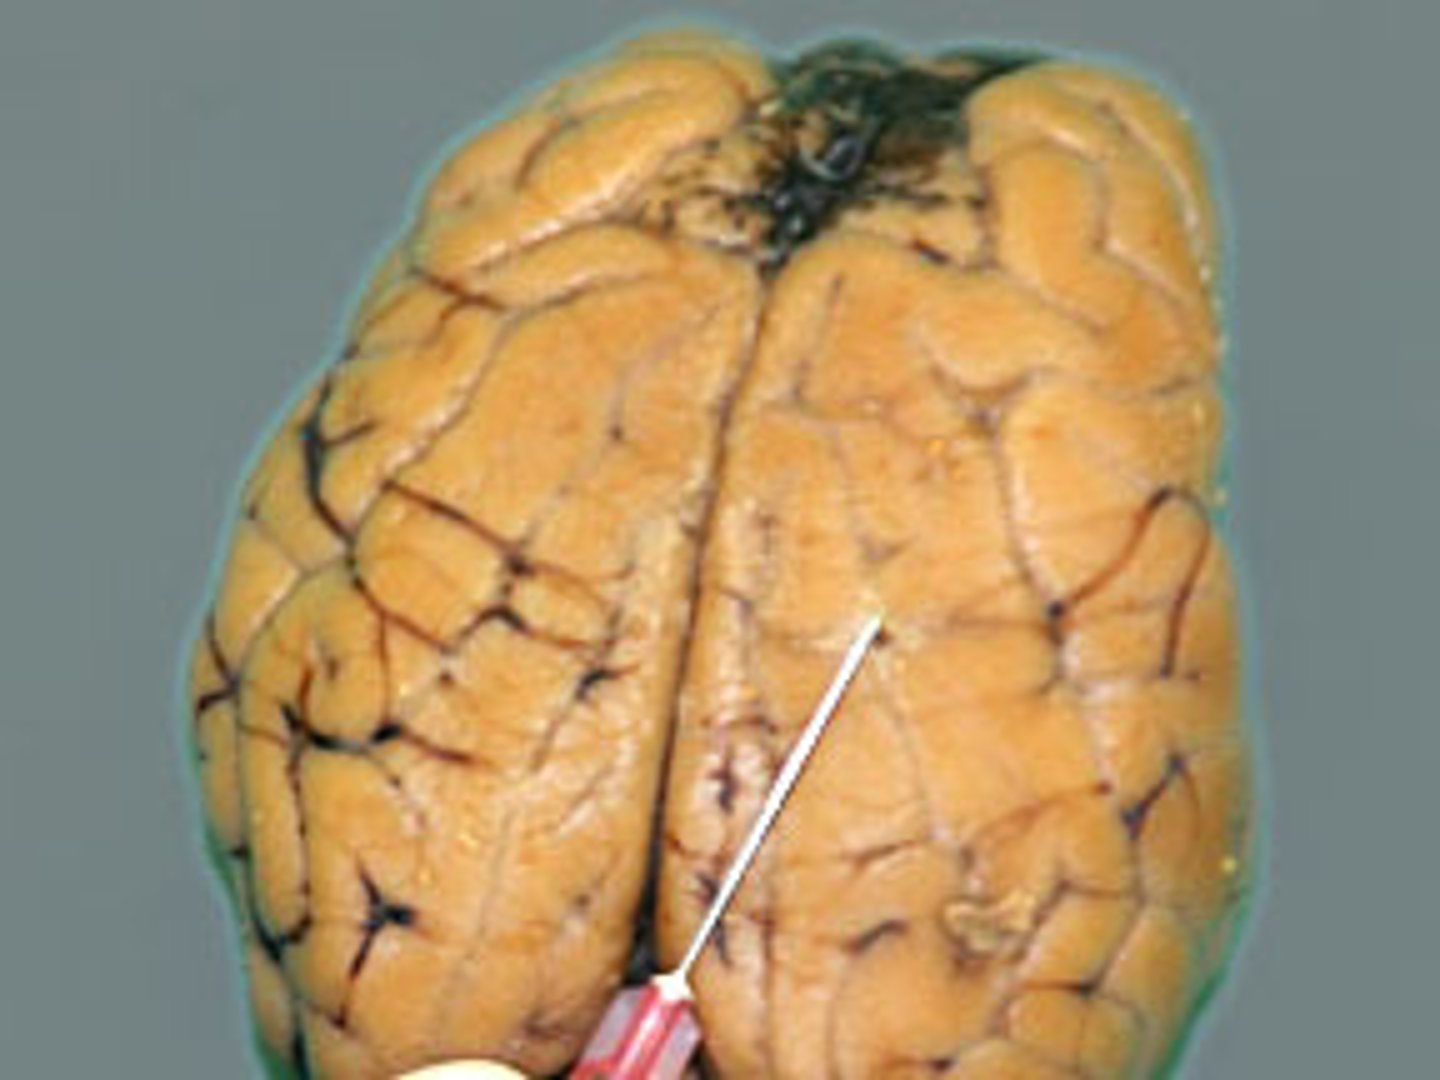

longitudinal fissure

Deep groove that separates the right and left hemispheres (#9)

Right hemisphere

The right side of the cerebrum (#10)

Left hemisphere

The left side of the cerebrum (#8)